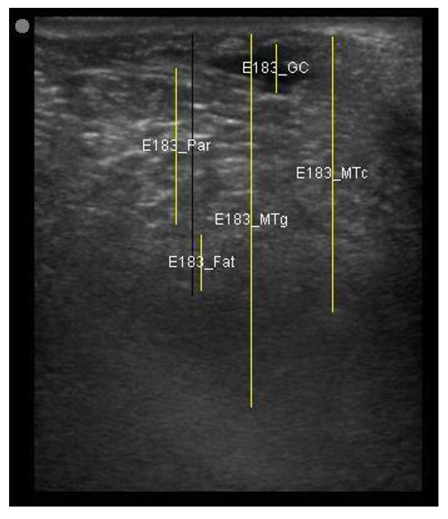

A minimum of three images were taken from each udder half. Images included the gland cistern, mammary parenchyma, putative fat pad and the boundary between the mammary gland and the abdominal wall. One image of suitable resolution per udder half, where all structures were identifiable and present was selected for image processing [27]. Udder halves with an udder palpation score of 4 or 5 (Table 1) at a specific time point (P107, L29 or L100) were considered “abnormal” [23] and were not included in the image selection (heavy: 1 ewe with 1 half and control: 2 ewes with 1 half each).

The image processing was undertaken using ImageJ software [28] as used by Abràmoff et al. [29]. The scales between pixels and millimetres were calculated based on the number of pixels, the scanning depth (mm), and the transducer width (mm) (Figure 4). This method relies on the ability of the operator to interpret and identify lines on the images. To standardize the assessment compartment depth, drawing templates were created for each time point as used by Molenaar et al. [30] and included four representative images from four different yearling ewes with and without the lines drawn for each compartment (Appendix A). The total depth of mammary gland conservative (MTc) was the smallest likely demarcation (abdominal wall) of the mammary gland (Figure 5a), and total depth of the mammary gland generous (MTg) was the largest likely demarcation of the mammary gland visible on the image [30] (Figure 5a). The MTc, MTg, fat pad (FP), parenchyma (PAR), and gland cistern (GC) depths were estimated at the deepest point for each sub-compartment, excluding the skin layers, using the straight tracer (Figure 5a) and were expressed in millimetres.

Figure 5.

(a) Demonstration of delimitations of the mammary total depth conservative (MTc) and generous (MTg), mammary gland cistern (GC), parenchyma (PAR) and the fat pad (FP) and (b) Demonstration of randomly positioning of regions of interest (1, 2, 3) in the parenchyma.

Appendix A. Drawing Templates of Mammary Ultrasound Images in Late Pregnancy, Early Lactation and Weaning in Yearling Ewes

Drawing template of mammary ultrasound images in late pregnancy (107 days of pregnancy; P107) in four different yearling ewes.